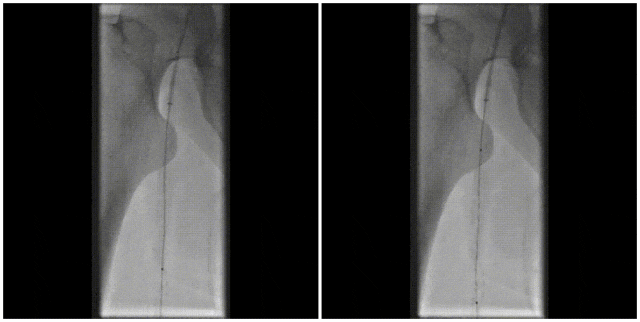

图:术中CT

图:术后CT

图:术后随访

图:术前CT